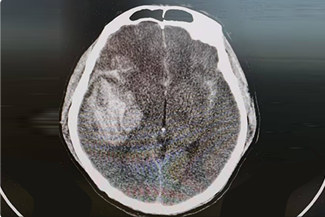

精通颅内动脉瘤介入栓塞和手术夹闭双技术,系统掌握脑动静脉畸形、颈内动脉海绵窦漏、硬脑膜动静脉漏等颅内血管疾病的诊疗和手术,精通颈动脉、椎动脉狭窄的血管内重建技术,以及颈动脉狭窄的内膜剥脱手术技术。在颅内肿瘤、椎管内肿瘤、颅脑损伤、高血压脑出血等疾病的诊治和手术,脑功能性疾病立体定向手术治疗等方面也积累了丰富的经验。

擅长脑血管病(出血与缺血)的神经介入与微创手术,能熟练开展脑外伤、重度颅脑损伤的救治工作。